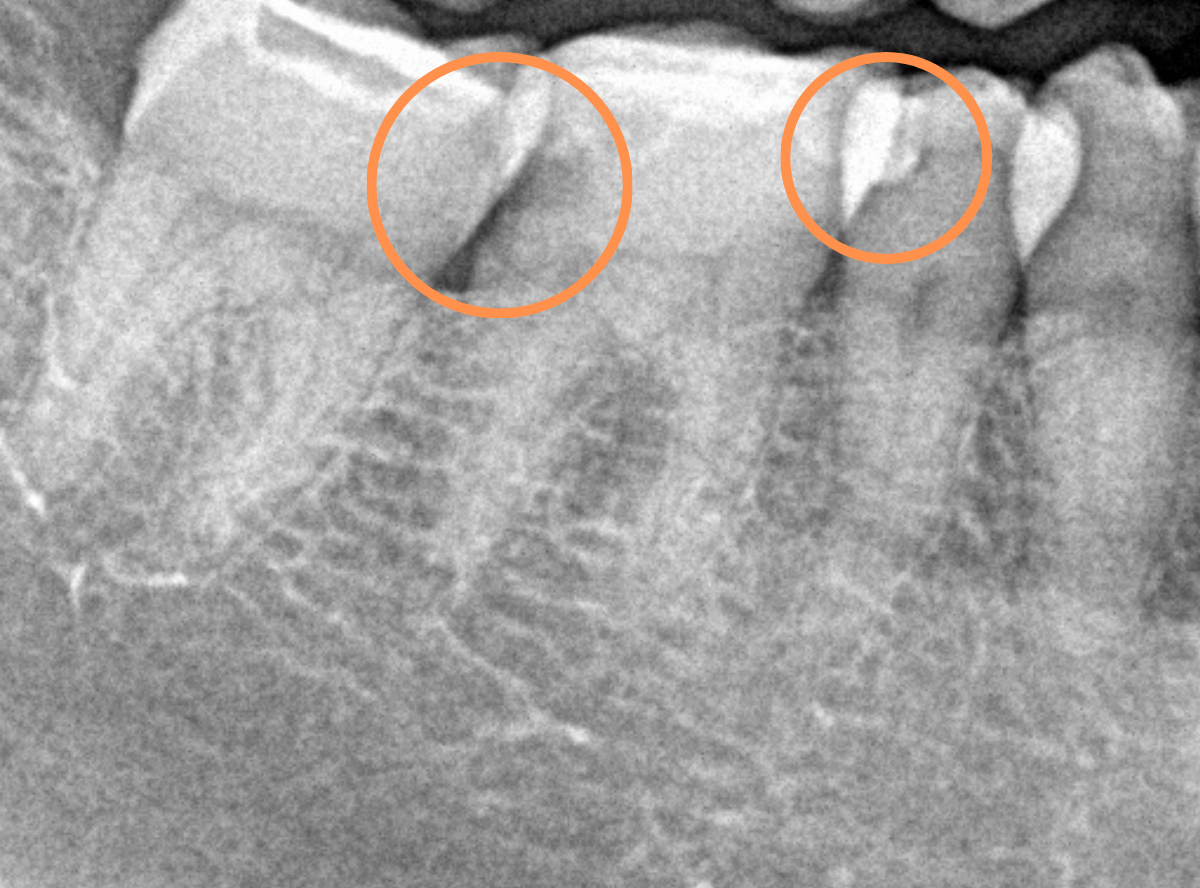

〇部が虫歯の部分です。

この写真からは深い虫歯があるのは想像つきません。

レントゲン写真で確認します。

青い線が神経、赤い線が虫歯の部分です。

前後の歯とも、かなり深く広い虫歯になっているのがわかります。